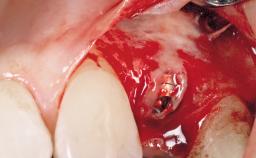

Late Placement of an Implant in a Maxillary Left Central Incisor Site

A 30-year-old female patient had lost tooth 21 and was referred to our clinic for consultation and treatment. Due to advanced apical infection, tooth 21 had been extracted two months earlier at another clinic and an acrylic-resin tooth had been bonded to the adjacent teeth. The patient desired implant treatment to avoid any damage to the adjacent natural teeth. While the patient had no history of any systemic disorder, she was a heavy smoker and exhibited medium to advanced periodontitis in the entire jaw. After the initial treatment to achieve a pocket probing depth of less than 4 mm and no bleeding on probing, a decrease in the height of the papillae mesial and distal to the extraction site and overall gingival recession were observed.

| Bone Augmentation | Horizontal|Staged |

| Augmentation Materials | Autogenous chips|Membrane |